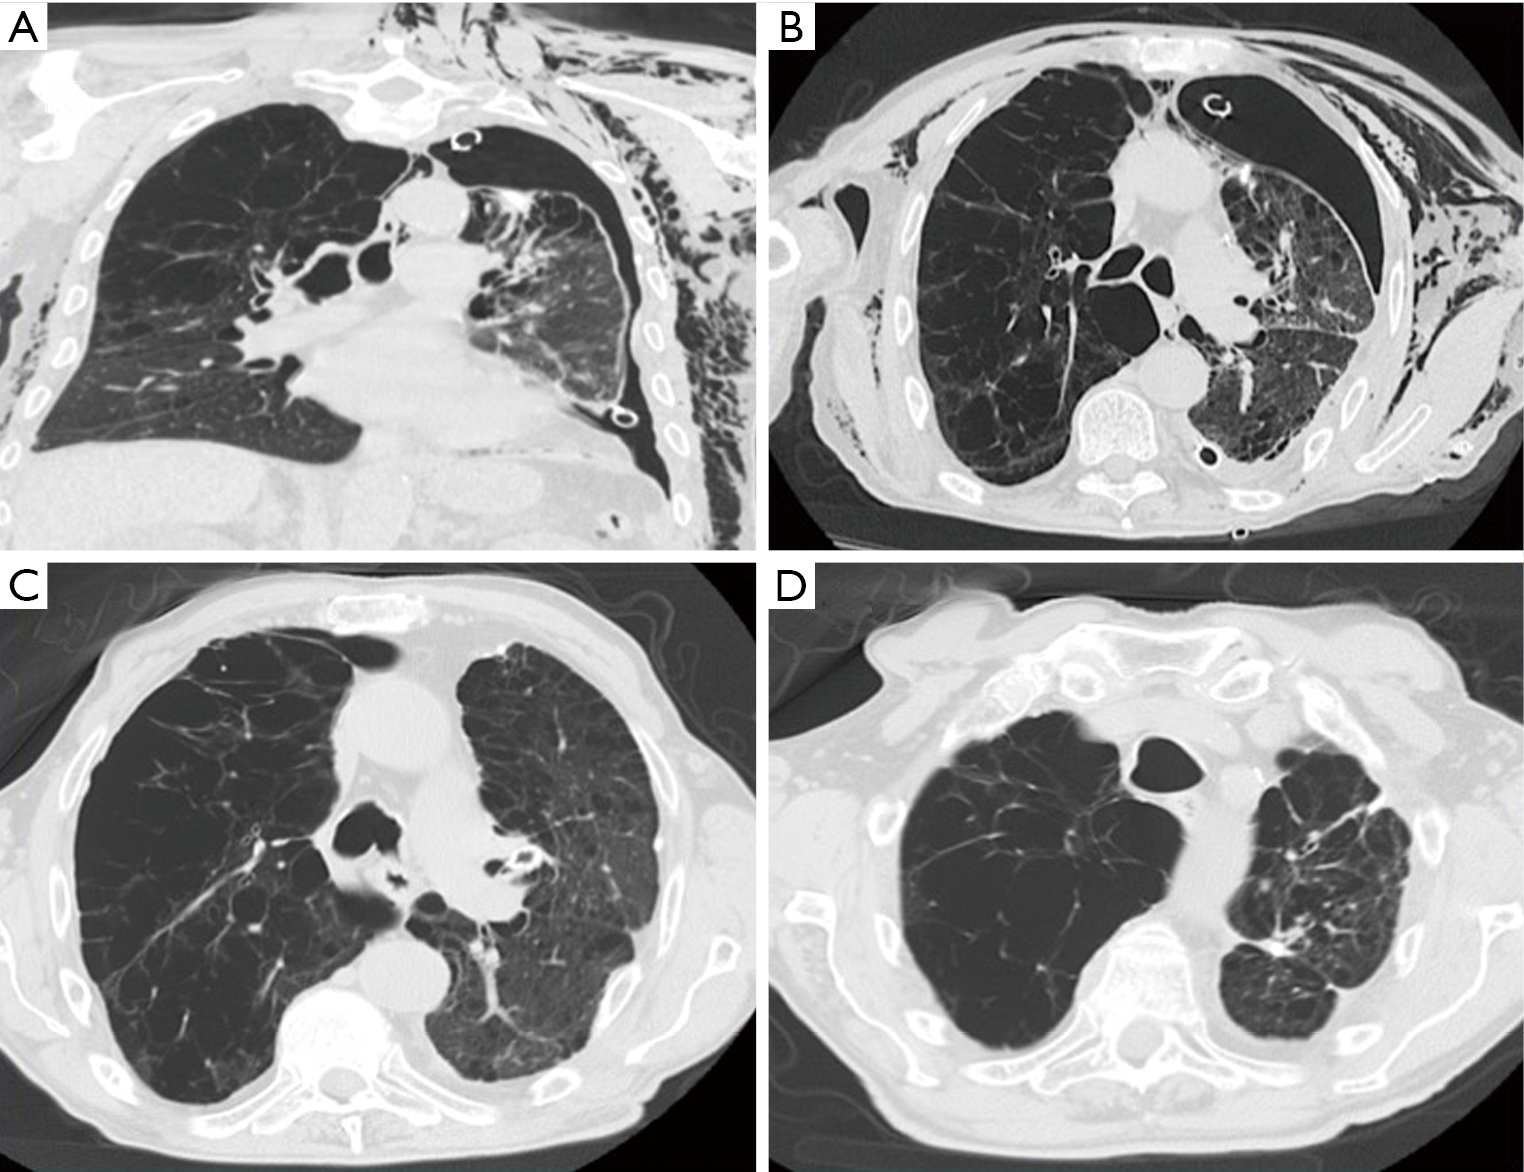

Figure 1 from The use of endobronchial valve device to eliminate air Endobronchial Valve Air Leak  Insertion of endobronchial valves for persistent air leaks aims to reduce or eliminate airflow through the leaks so that the rest of the lung can. Secondary spontaneous pneumothoraxes commonly occur in patients with cystic fibrosis (cf) and can be complicated by. Endobronchial valve (ebv) therapy, a validated method for bronchoscopic lung volume reduction (blvr) in severe emphysema, has. Prolonged hospitalization,. Endobronchial Valve Air Leak.